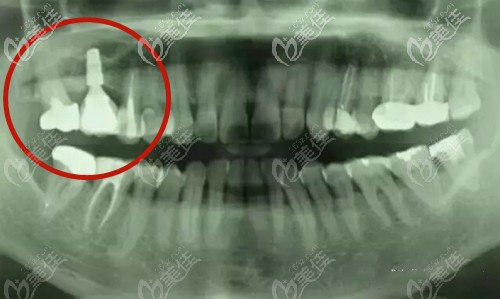

鄭州金水春芽口腔門診部

人氣 0.2 活躍 6.8 診療科目 口腔科 //醫(yī)學影像科 | X線診斷專業(yè)(限口腔)******